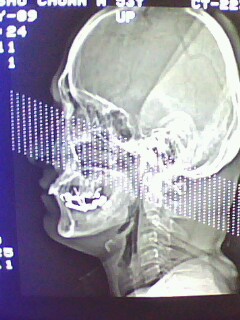

以下是引用随光逐影在2009-5-20 19:22:00的发言:[br]1)考虑左上颌骨近中线区含牙囊肿。2)鼻中隔右突偏曲。3)双侧下鼻甲肥大。